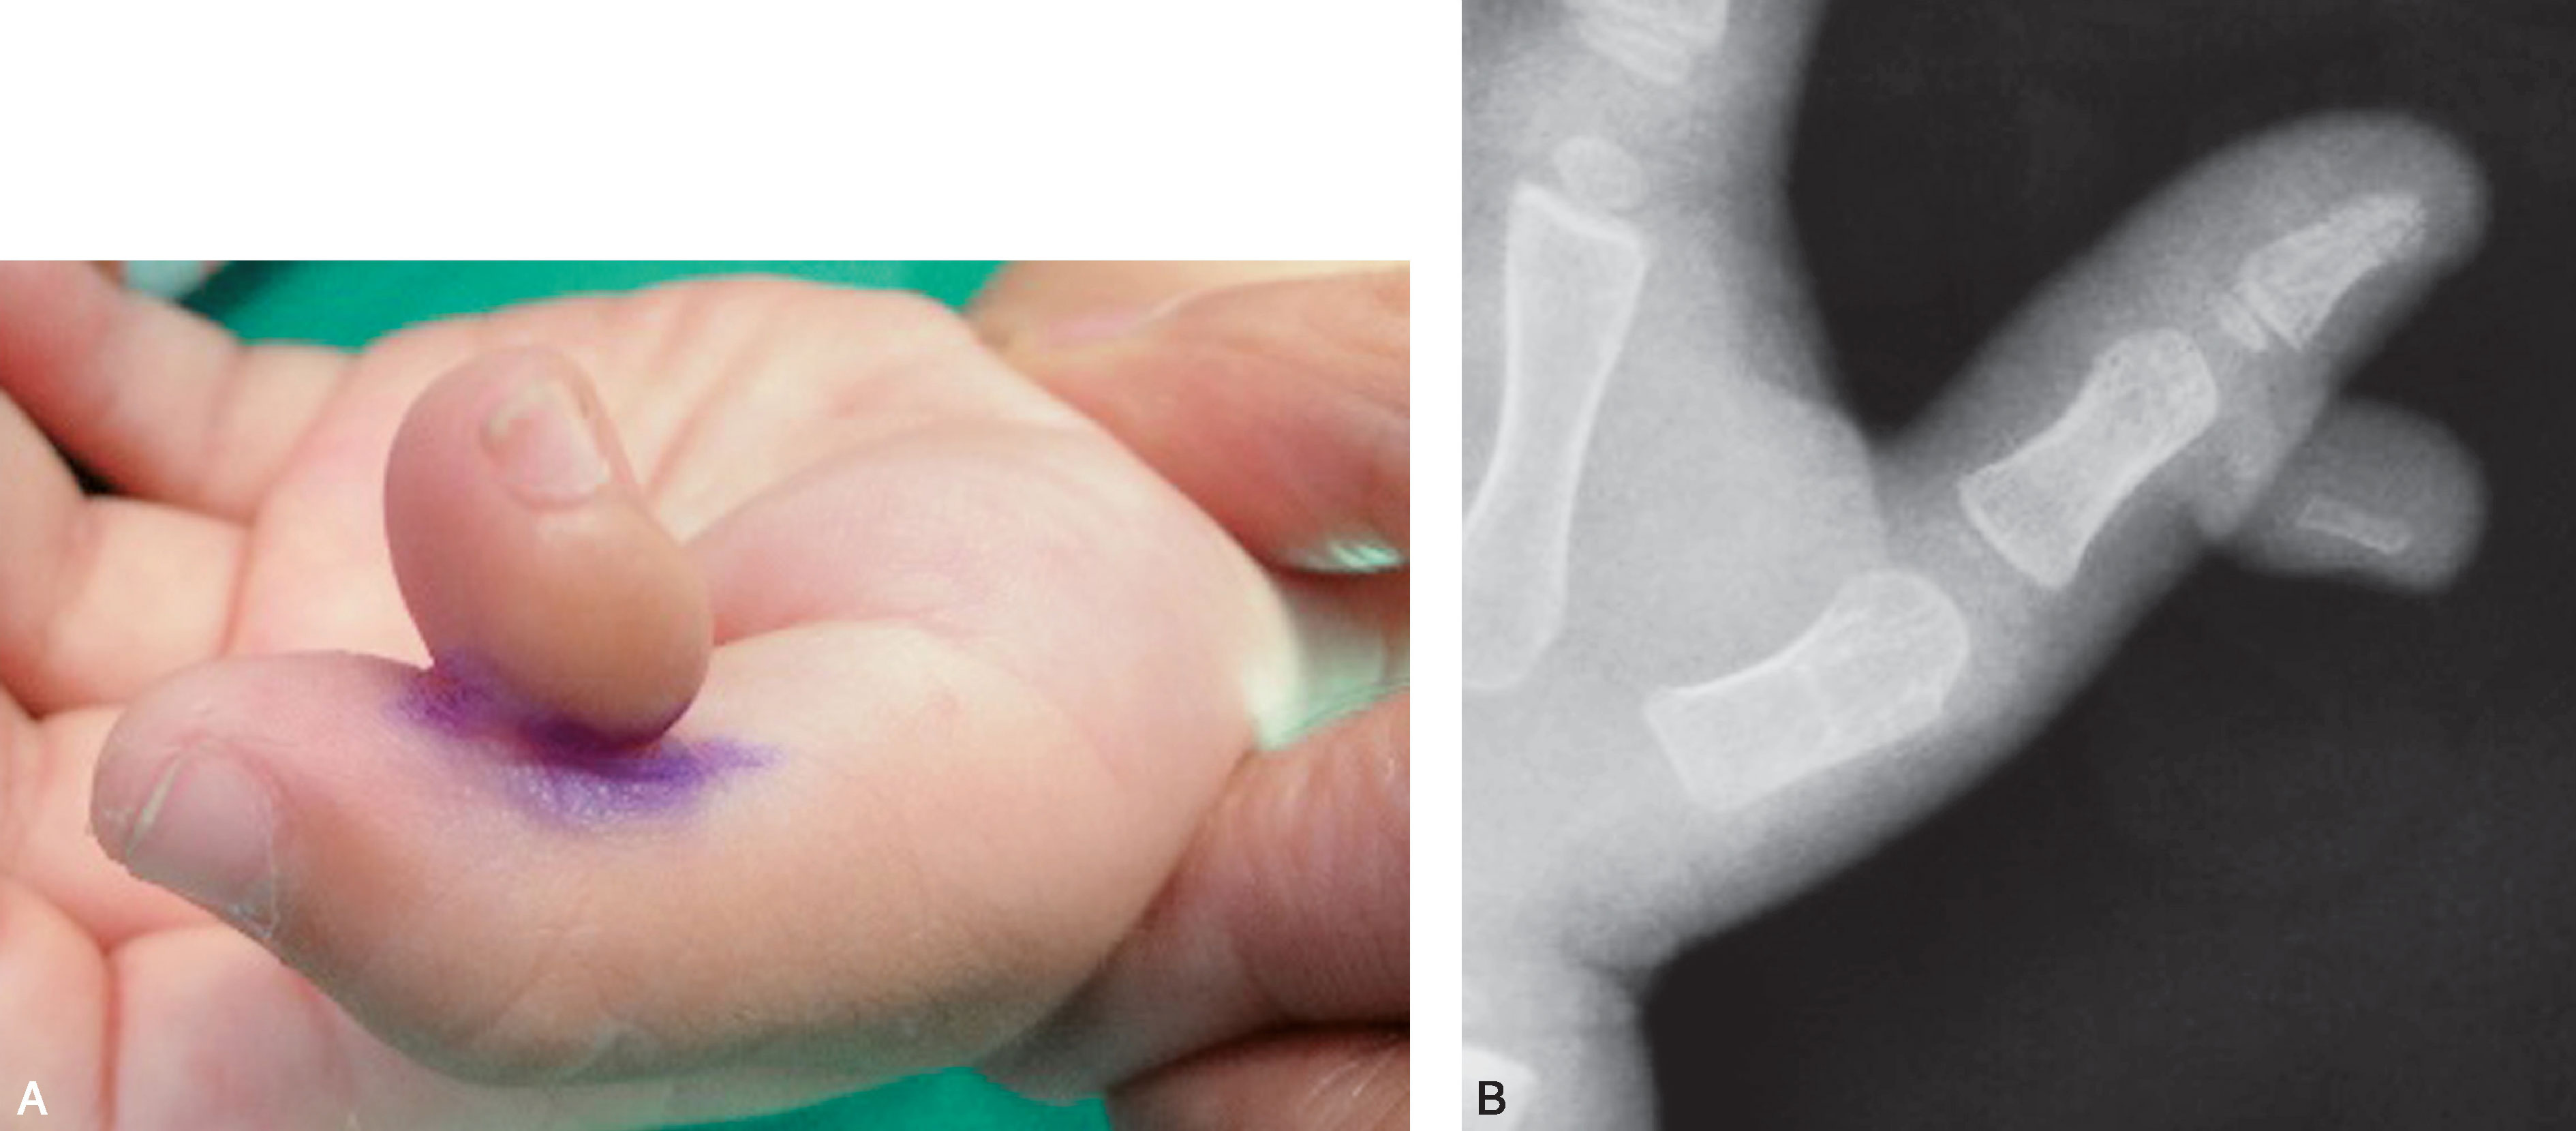

图2-1-3 Ⅰ型病例3

A.体位像显示主、次拇指指甲完全融合在一起,似一个指甲,应选择切除桡侧赘拇,然后需重建甲沟,并尽可能与对侧对称;B.X 线片显示,远节指骨分叉,桡侧部分细小,切除容易,但切除后应注意保持主拇指基底桡侧骨骺板开放。 由于远节指骨基底骨骺为不正常的倒V 形,术后骨骺生长仍可能异常,导致保留下来的远节指骨偏斜,需进一步截骨矫正